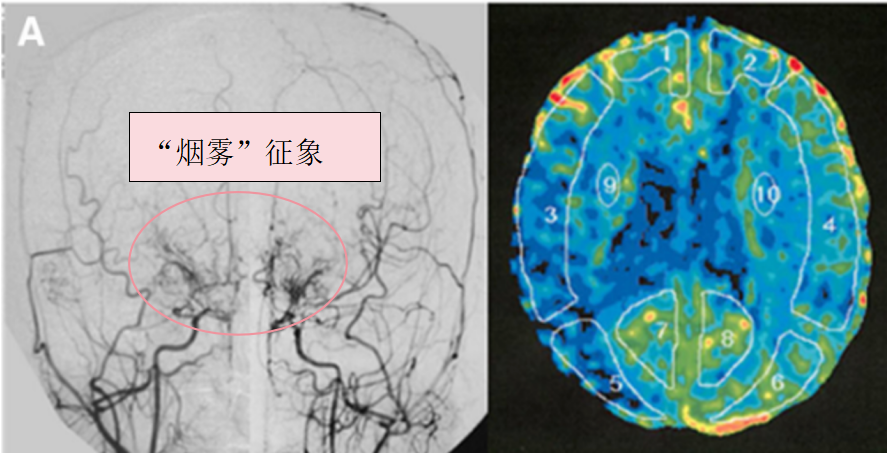

烟雾病,是一种罕见的脑血管疾病,主要表现为脑基底动脉末端的狭窄或闭塞,以及颈内动脉末端与大脑动脉吻合支的形成。这种疾病会导致脑部供血不足,进而引发一系列严重的症状。 其中...

烟雾病 (Moyamoya disease)是一种罕见的脑血管疾病,表现为颅内主要动脉的逐渐狭窄,并伴有侧支血管网的形成。此病的治疗时机至关重要,通常基于病情的严重程度和临床表现来决定。 8岁的Ho...

出血型烟雾病(MMD) 虽少见,但这种疾病的凶险之处在于,患者异常增生的烟雾血管随时可能引爆导致脑出血。而原本供血不足的血管系统又像年久失修的水管,稍有不慎就会引发脑梗。 血管重...